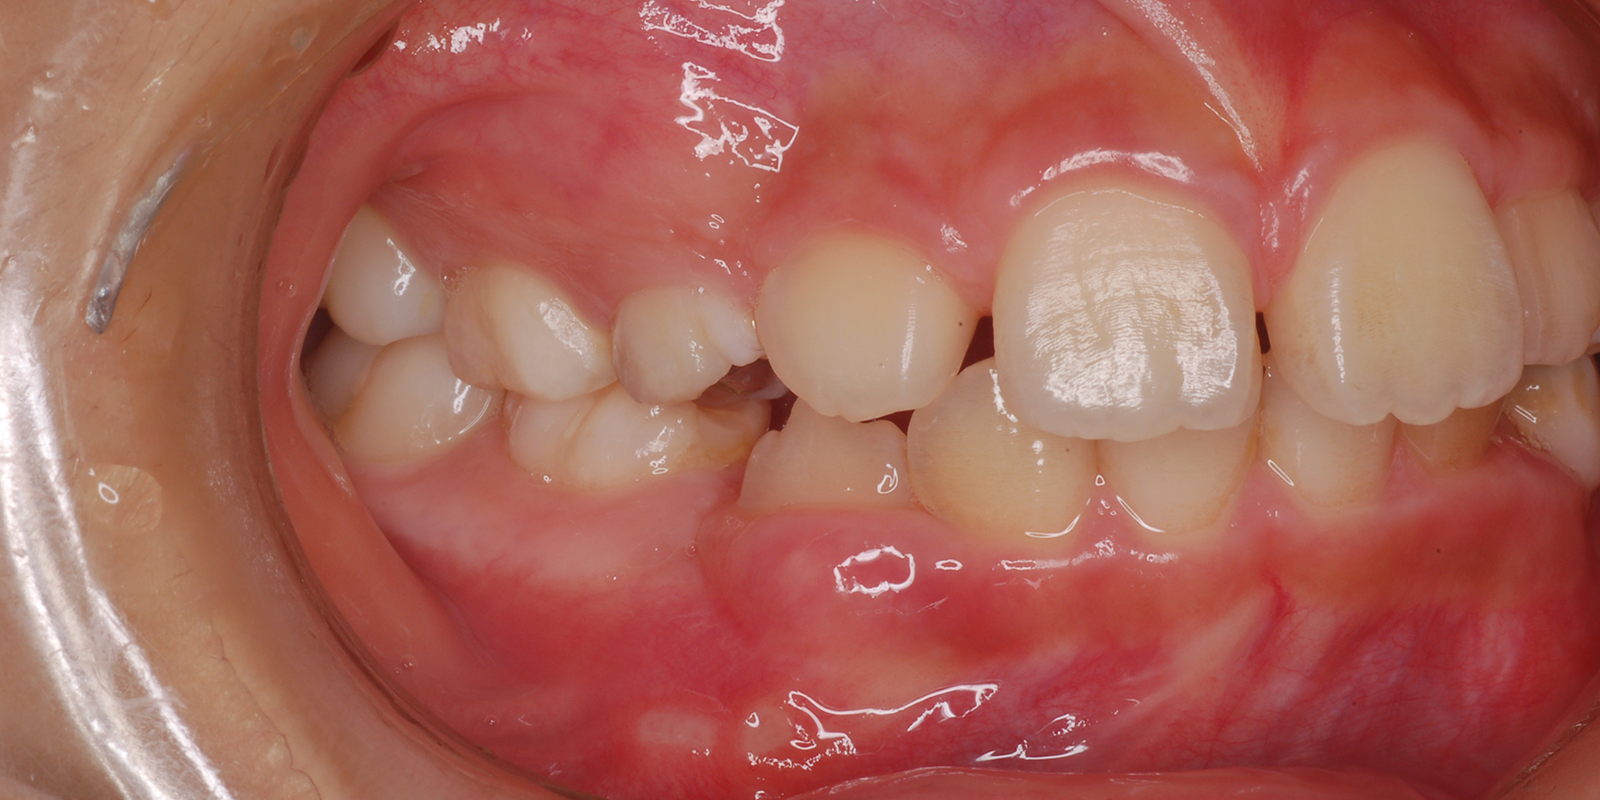

術前

| 主訴 | 叢生 |

|---|---|

| 診断 | アングルⅡ級1類 |

| 初診時年齢 | 9歳10か月 |

| 装置 | ヘッドギアー(1期治療) 若干上顎が大きく、大臼歯関係が上顎大臼歯が前に出て上顎前突のため、上顎大臼歯を遠心に送るためヘッドギアーを使用しました。 |

| 抜歯・非抜歯 | 上下左右第1小臼歯を抜歯、マルチブラケット(2期治療) 大臼歯関係が正しい関係になりましたが、叢生、歯軸の関係が悪いので、永久歯の抜歯を行いました。 |

| 治療期間 | 1期治療:1年10ヶ月 2期治療:3年 |

| 通院回数 | 1期治療:13回 2期治療:約36回 |

| 治療費 | 約100万円 矯正歯科治療は公的医療保険の適用外の自費(自由)診療となります |

| 治療のリスク | ・装置を使用しなければ効果が出ない ・歯に痛みが出ることがある ・取り外しのため、なくすことがある ・ブラッシングが悪い場合虫歯や歯肉炎になります |